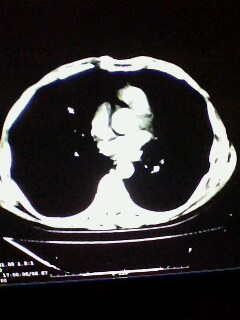

标题: CT28315:咳嗽咳痰咯血半月并胸痛 [打印本页]

标题: CT28315:咳嗽咳痰咯血半月并胸痛

1、纵膈窗效果不好,初步考虑左肺下叶感染性病灶,建议正规抗炎治疗后复查   2、右肺下叶陈旧性病灶伴局部胸膜增厚。

考虑左肺下叶周围型肺癌.图象欠清,请问病人贵更?

考虑左肺下叶周围型肺癌.

图像资料欠清,建议强化,考虑周围型肺癌。

左下肺肿块影,深分叶,考虑肺癌。

左下肺球形病灶,考虑:1:球形肺炎;2:周围型肺癌不除外,建议治疗后复查

不排除左肺下叶周围型肺癌可能!建议穿刺活检!

考虑左肺下叶周围型肺癌并阻塞性肺炎。